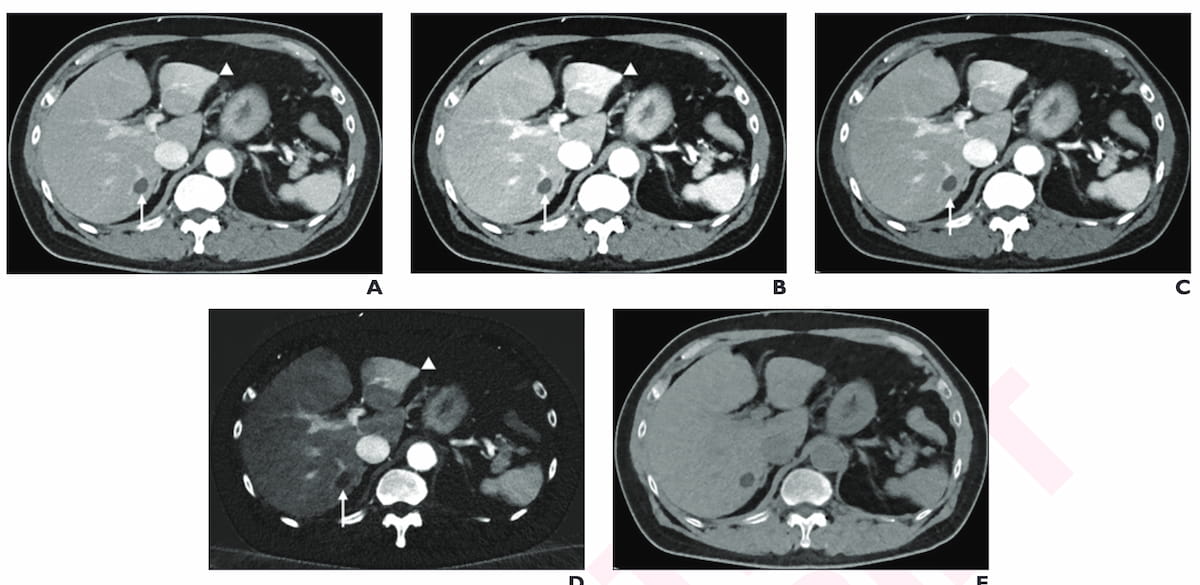

New research suggests the combination of multiparametric dual-energy CT and deep learning image reconstruction for liver metastases detection enables a 45 percent reduction in radiation dosing.